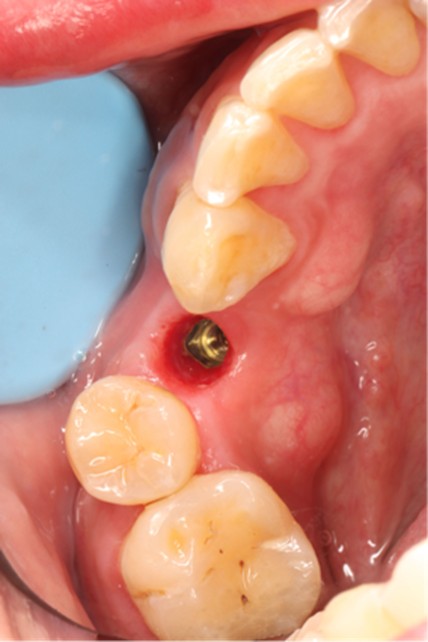

November 23, 2025: Implant follow-up examination. The implant surgical site showed excellent healing, with no abnormal bone density around the implant and satisfactory osteogenesis. The third-stage impression taking was implemented. The panoramic radiograph below confirmed the complete seating of the implant impression coping.

December 4, 2025: Definitive crown delivery. The margin of the implant-supported crown exhibited optimal adaptation.